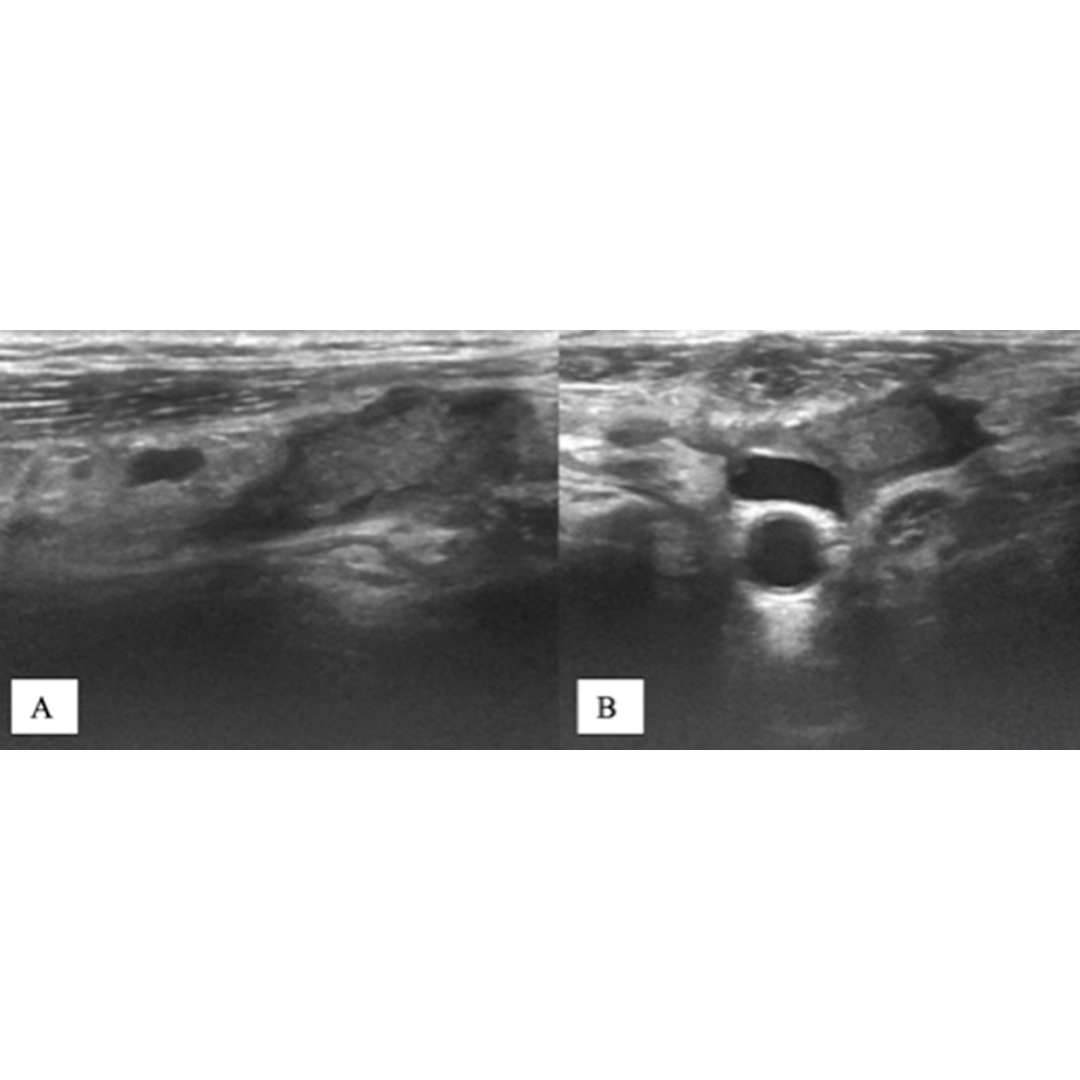

Presencia de agentes hemostáticos en lecho tiroideo

En algunas tiroidectomías los cirujanos optan por usar agentes hemostáticos como Gelfoam (marca Pfizer), Gelita Hemospon o Surgispon, un material de esponja de gelatina indicado en procedimientos quirúrgicos como un auxiliar para la hemostasia, cuando el control del sangrado mediante procedimientos convencionales no es efectivo o resulta impracticable.

Un paciente que se realiza una ecografía dentro de las 6 semanas posteriores a la cirugía y luego de haber recibido esta esponja gelatinosa probablemente aún no se encuentre absorbida en su totalidad, y la observemos bajo Ecografía como una imagen hiperecogénica generando muchas veces imágenes similares a un remanente de tejido tiroideo, similares a un absceso o bien simular una recidiva local.

Conocer la historia clínica del paciente y la data de la cirugía son relevantes para diferenciarlos.

Hallazgos ecográficos esperables para diferenciar una esponja gelatinosa hemostática de un remanente tiroideo:

• Imagen hiperecogénica homogénea

• No vasculariza al Doppler

• No presenta ecoestructura de parénquima similar a la glándula tiroidea. En caso de dudas siempre podemos usar de referencia las glándulas submandibulares para comparar el parénquima.

• Se presenta sólo dentro de las primeras 6 semanas posteriores a la cirugía, éste antecedente es fundamental para su existencia.

Figura 5. Ecografía transversal (A) y longitudinal (B) de una paciente de 33 años tras tiroidectomía y disección del compartimento central por CAP. Las Ecografías, obtenidas 21 días después de la cirugía, muestran un nódulo ecogénico alargado en el lecho de la lobectomía izquierda (flechas) simulando un remanente tiroideo. El nódulo ya no estaba presente en la ecografía de control realizada 14 meses después de la tiroidectomía, ya que la esponja gelatinosa Gelfoam se encontraba reabsorbida.